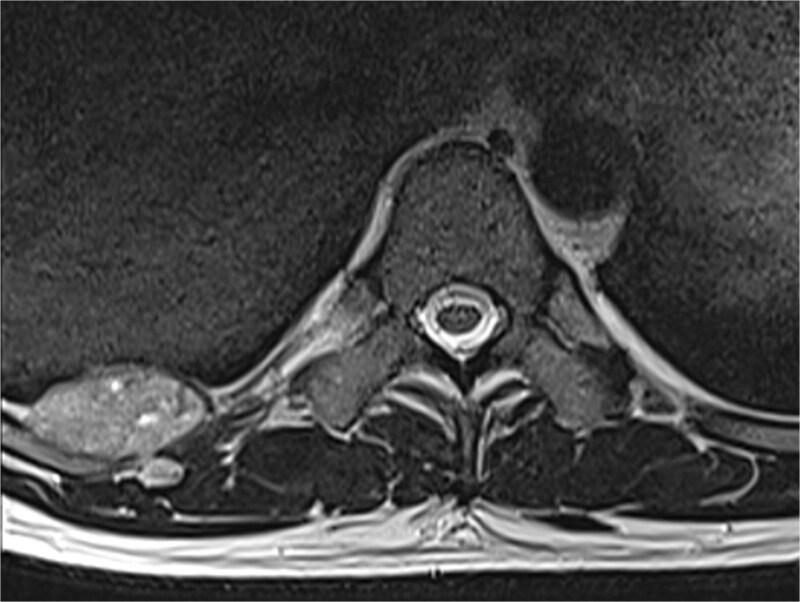

Glomus tumors are rare neoplasms that usually appear in subungual locations. A primary glomus tumor in the chest wall is extremely rare. We present a case of a 42-year-old male with intermittent pain under the right scapula for approximately a year. No skin lesions were observed. A magnetic resonance imaging and computed tomography scan showed a well-defined subpleural lesion on the right side of the chest along the ninth intercostal space. The tumor was removed via video-assisted thoracic surgery. The pathological report revealed a glomangioma. We analyzed in detail existing cases of glomus tumors in the chest wall. The chest wall is a possible site of a glomus tumor, which doesn't have any specific clinical or radiological signs. Radical surgical removal should be the treatment of choice.

血管球瘤是一种罕见的肿瘤,通常出现在甲下部位。胸壁原发性血管球瘤极为罕见。我们报告一例42岁男性,右肩胛下间歇性疼痛约一年。未观察到皮肤病变。磁共振成像和计算机断层扫描显示右侧胸壁沿第九肋间有一个边界清晰的胸膜下病变。通过电视辅助胸腔镜手术切除肿瘤。病理报告显示为血管球瘤。我们详细分析了胸壁血管球瘤的现有病例。胸壁是血管球瘤的一个可能发生部位,没有任何特定的临床或放射学征象。根治性手术切除应是首选治疗方法。